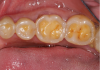

The BEWE is a scoring system that evaluates the most severely affected surface in each sextant, recording one of the four-level scores as follows30: 0 = no erosive tooth wear (Figure 8); 1 = initial loss of surface texture (Figure 9); 2 = distinct defect, hard-tissue loss <50% of surface area (Figure 10); 3 = hard-tissue loss ≥50% of surface area (Figure 11). (Scores 2 and 3 often involve dentin.) After all sextants are assessed, the sum of scores provides the risk level of each patient and may help guide the design of a professional management program for the patient.

Fig 8. BEWE scoring system: score 0 = no erosive tooth wear (Fig 8); score 1 = initial loss of surface texture (Fig 9); score 2 = distinct defect, hard-tissue loss <50% of surface area (Fig 10); score 3 = hard-tissue loss ≥50% of surface area (Fig 11)

Fig 9. BEWE scoring system: score 0 = no erosive tooth wear (Fig 8); score 1 = initial loss of surface texture (Fig 9); score 2 = distinct defect, hard-tissue loss <50% of surface area (Fig 10); score 3 = hard-tissue loss ≥50% of surface area (Fig 11)

Fig 10. BEWE scoring system: score 0 = no erosive tooth wear (Fig 8); score 1 = initial loss of surface texture (Fig 9); score 2 = distinct defect, hard-tissue loss <50% of surface area (Fig 10); score 3 = hard-tissue loss ≥50% of surface area (Fig 11)

Fig 11. BEWE scoring system: score 0 = no erosive tooth wear (Fig 8); score 1 = initial loss of surface texture (Fig 9); score 2 = distinct defect, hard-tissue loss <50% of surface area (Fig 10); score 3 = hard-tissue loss ≥50% of surface area (Fig 11)